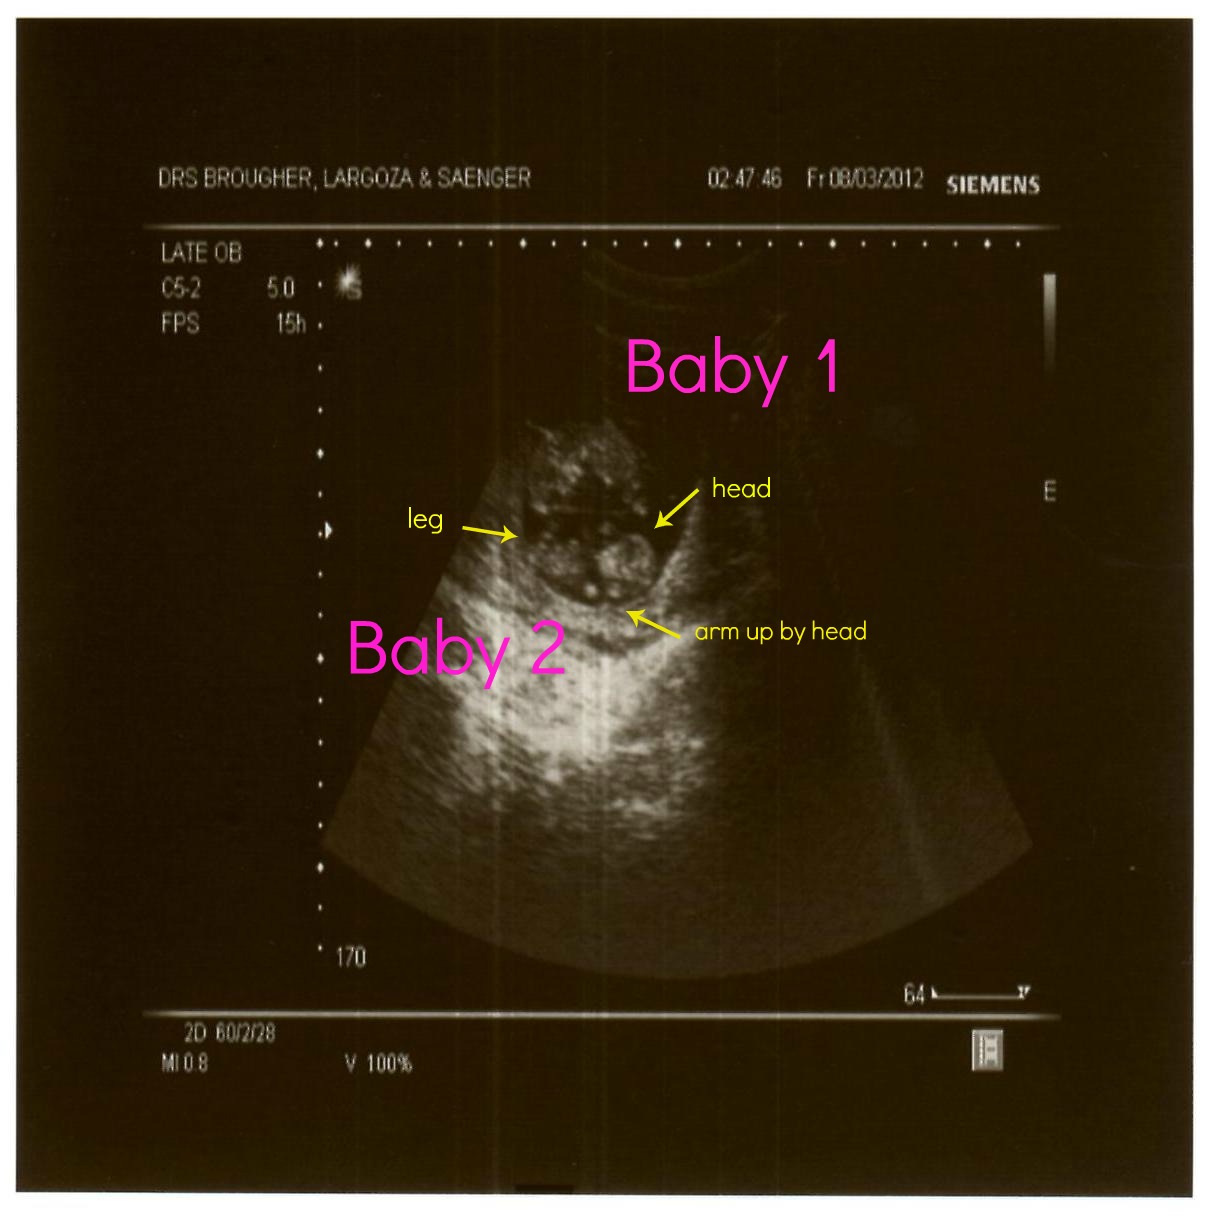

Best moment this week: Getting to see my babies moving again!

This Week in my Belly:

This week's big developments: Your baby can now squint, frown, grimace, pee, and possibly suck his thumb! Thanks to brain impulses, his facial muscles are getting a workout as his tiny features form one expression after another. His kidneys are producing urine, which he releases into the amniotic fluid around him — a process he'll keep up until birth. He can grasp, too, and if you're having an ultrasound now, you may even catch him sucking his thumb.

In other news: Your baby's stretching out. From head to bottom, he measures 3 1/2 inches — about the size of a lemon — and he weighs 1 1/2 ounces. His body's growing faster than his head, which now sits upon a more distinct neck. By the end of this week, his arms will have grown to a length that's in proportion to the rest of his body. (His legs still have some lengthening to do.) He's starting to develop an ultra-fine, downy covering of hair, called lanugo, all over his body. Your baby's liver starts making bile this week — a sign that it's doing its job right — and his spleen starts helping in the production of red blood cells. Though you can't feel his tiny punches and kicks yet, your little pugilist's hands and feet (which now measure about 1/2 inch long) are more flexible and active.